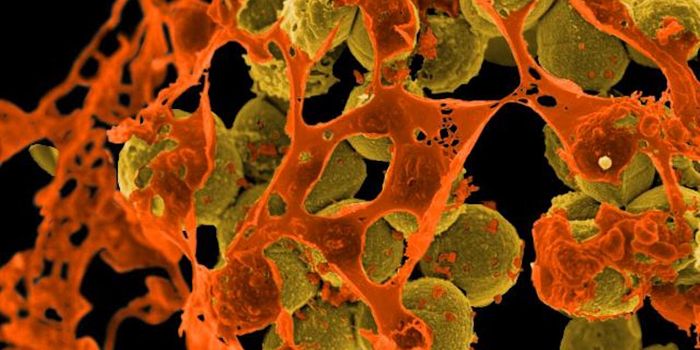

OCT 29, 2016Clinical & Molecular DXDespite frequent cleaning and sterilization, hospitals are notorious hotspots for germs and pathogens. And it’s no ...